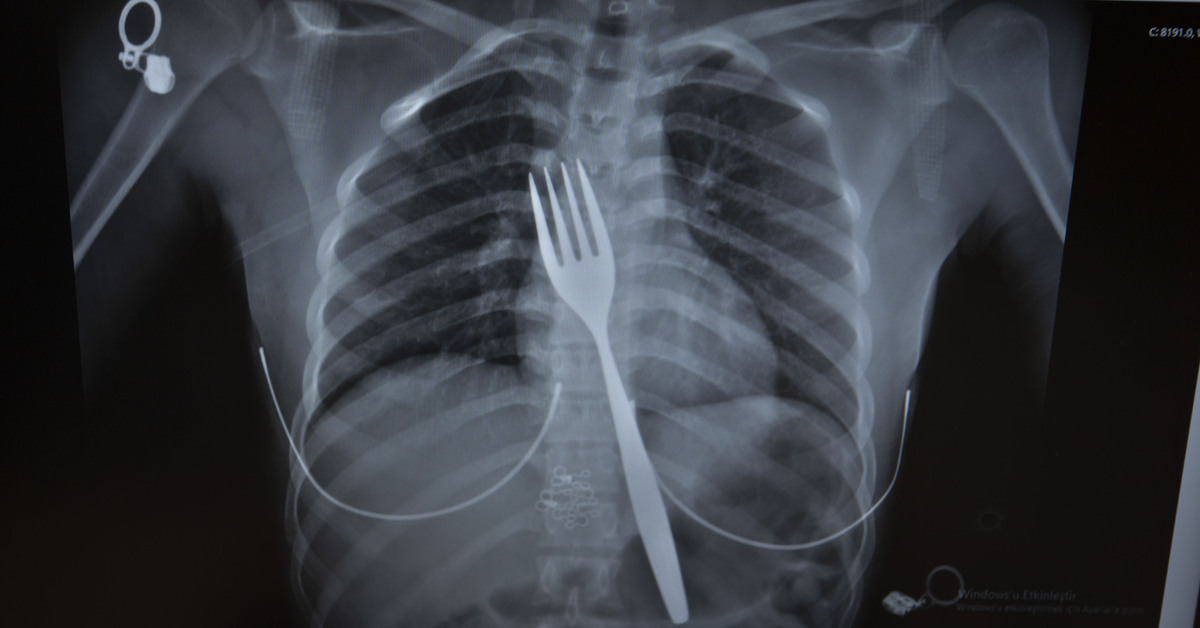

Burada röntgeni çekilen hastanın yemek borusunda 18 santimlik çatal olduğu tespit edildi.

Vakayı ilk duyduğunda şaşırdığını anlatan Edizsoy, “Büyük bir çatalın tamamen yutulması şeklinde ortaya çıkan bu vakayı ilk duyduğumda doğru olmadığını düşündüm. Hasta 18 yaşında ve yabancı uyrukluydu. Türkçesi biraz zayıf olduğu için belki de yanlış anlaşılmalar olabileceğini düşündük. Ama hastanın filmini çektiğimizde gerçekten bir çatalın yemek borusunda olduğunu gördük” dedi.

Yemek borusu yaralanmasının ölümle sonuçlanabileceğini vurgulayan Edizsoy, şöyle devam etti: “Biz en çok bu yüzden tedirgin olduk. Ama ciddi bir yaralanma olmadığını da yapılan endoskopiyle gördük. Endoskopi ile çıkarılamadı çünkü oldukça büyüktü ve endoskopik aletler için uygun değildi. Bu büyük bir yemek çatalı olduğu için kendi ağırlığı da var. Bir çivi gibi, iğne gibi tutulup çekilemiyor. Bundan dolayı karında yapılan kesi ile mideye ulaşıp midenin içinden bunu çıkarmak şeklinde bir strateji izledik. Yaptığımız bu ameliyatla da bu çatalı oradan çıkarabildik.”